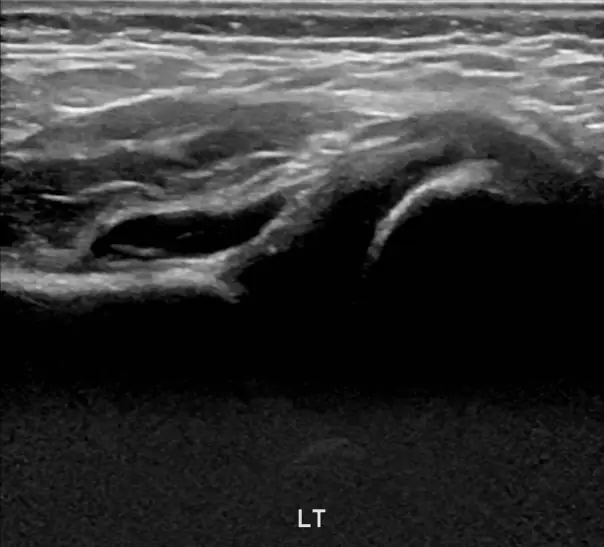

안녕하세요! 오늘은 아기 허벅지 주름이 비대칭이거나 이상하게 보일 때 꼭 체크해야 하는 내용을 알려드릴게요. 신생아나 영아의 허벅지에 자연스럽게 생기는 주름이지만, 깊이나 위치가 다르면 발달성 고관절 탈구의 신호일 수 있어요. 이 질환은 태어날 때부터 허벅지뼈가 골반에 잘 맞물리지 않는 상태로, 방치하면 걷기 어려움이나 다리 절름발이로 이어질 수 있어요. 다리 길이 차이, 다리 움직임의 이상, 걷기 시 불편함 등 증상이 있다면 빠른 검사가 필요합니다. 초음파 검사는 4주에서 6개월 사이에 가장 효과적이며, 방사선 걱정 없이 안전하게 아기 허관절 구조를 확인할 수 있어요. 조기 발견 시 간단한 치료로 정상 성장 가능하니, 아기 허벅지 주름이 이상하게 보인다면 꼭 전문가의 검진을 받아보세요. 건강한 성장과 걷기를 위해 작은 관심이 큰 차이를 만듭니다.